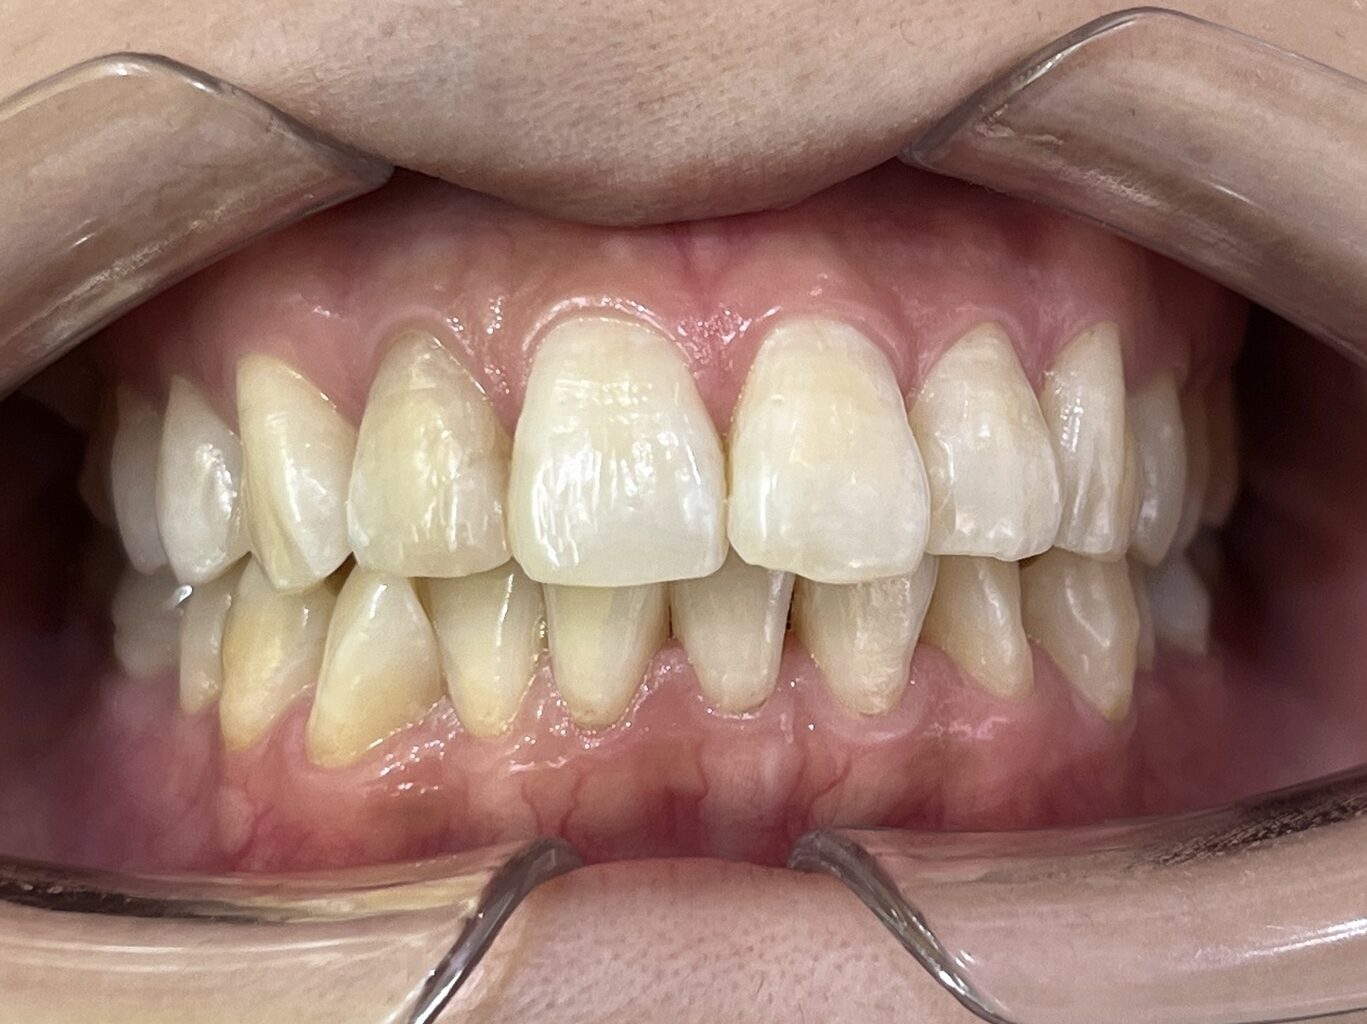

叢生の症例3(マウスピース矯正)

治療前後(BEFORE/AFTER)

| 年齢 | 10代女性、叢生、八重歯 |

| 主訴 | 八重歯、歯のガタガタ |

| 診断 | 叢生 |

| 治療方法 | 上下・マウスピース矯正(抜歯はしていません) |

| 治療期間 | 約2年 |

| 費用総額 | 1,100,000円(税込) |

| リスク・副作用 | 痛み/歯根吸収/歯肉退縮/後戻り など |

本症例では八重歯がかなり出ている叢生状態でした。

下顎前歯のガタガタも併せて治したいというご希望でした。

抜歯も検討しましたが、スキャナーによるシミュレーション、精密検査により歯列のスペースを確保しかみ合わせも意識しながら歯並びを整えるため、抜歯をしないで矯正治療を行いました。

思春期で難しいながらもマウスピース矯正で行い治療後は歯並びとかみ合わせが改善し、

見た目だけでなく歯磨きもしやすい状態になりました。